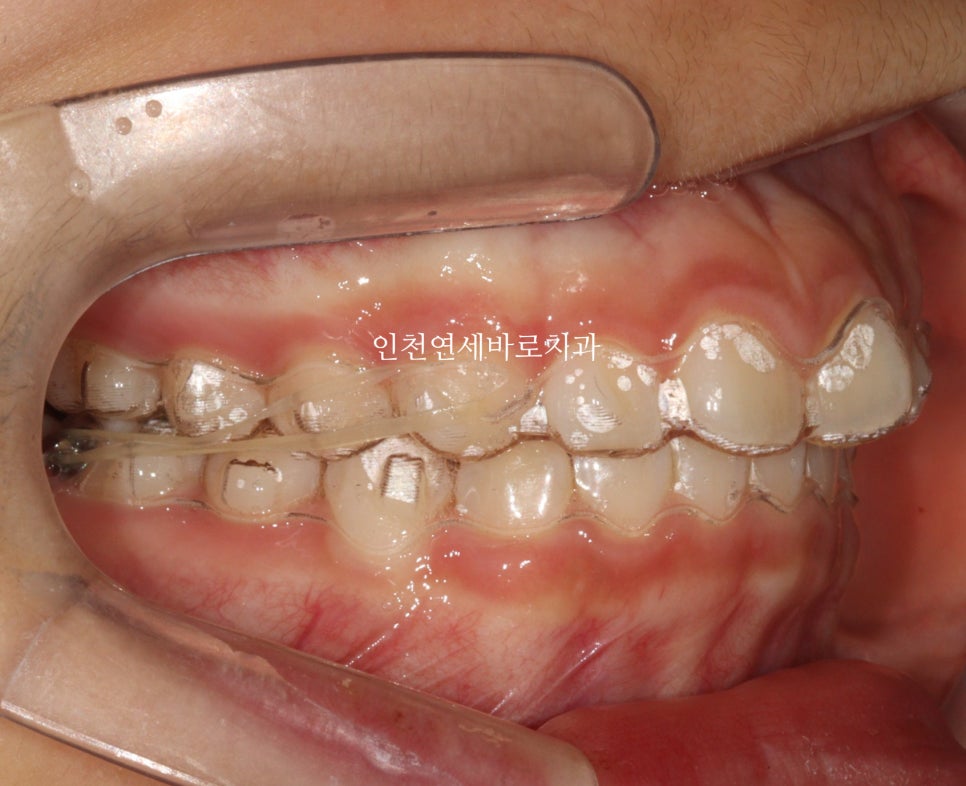

환자 초기 상태

인천연세바로치과에 온 환자아이입니다.

앞니가 튀어나와있고, 삐뚤삐뚤, 그리고

#과개교합

도 있는 아이었습니다.